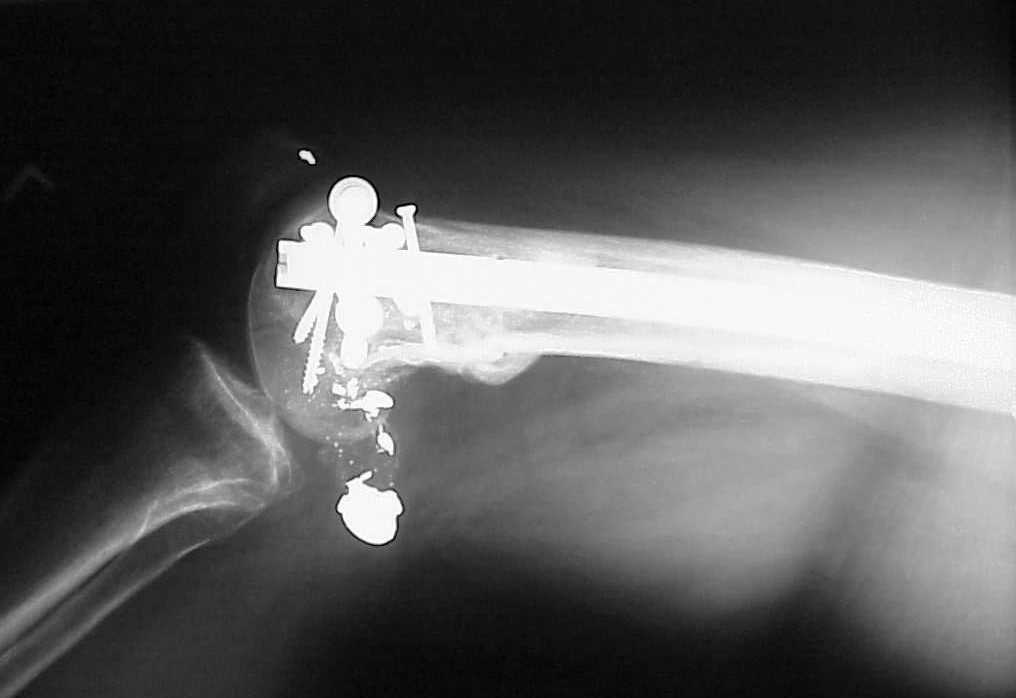

A CT and knee xrays would help identify lateral condyle comminution and/or a "hoffa fragment" of the posterior condyle. I am concerned that the lateral cortex is not sufficient to give purchase for a retrograde IMN. blocking screws could improve this as a possibility. A long blade or LISS if avaible would be my secondary choices. Good luck. Any chance you can get these cases transferred earlier when it

See attached case that was done several years ago before LISS. He had comminuted trochlea and anterior blocking screws were used to prevent anterior IMN cut-out.